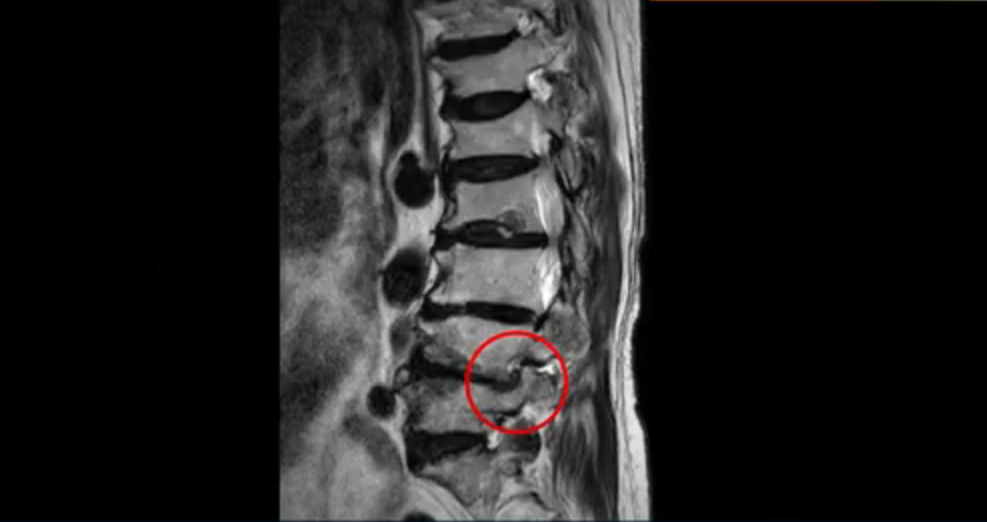

이 환자분은 허리 여러 마디가 다 안 좋아서 오랫동안 허리가 아프셨고 허리도 일찌감치 굽으셨습니다. MRI를 보시면 허리 여러 마디가 심하게 안 좋습니다.

보시다시피 4번 5번 마디에는 심한 중심성 협착이 있고

1번 2번,

2번 3번,

3번 4번에도 중심성 협착이 있습니다.

또 신경 가지가 빠져나가는 추간공도 좁아져 있습니다. 이런 이유로 환자분의 다리가 저리고 아픈 겁니다.

또한 척추뼈 여러 개가 압박 골절과 변형으로 찌그러져 있고

골다공증도 심하시고 보시다시피 근육량이 너무 적습니다. 근육이 정상적인 분들과 비교해보면 근육이 얼마나 적은지 알 수 있습니다.